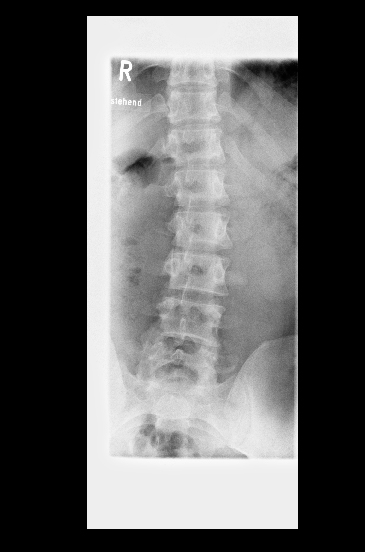

Das bringt mich zu meinem eigentlichen Punkt: Ich habe aktuelle Röntgenaufnahmen anfertigen lassen. Der zuständige Orthopäde meinte, mein Krümmungswinkel LWS läge bei 22 Grad. Vor knapp zehn Jahren hieß es, es seien 12 Grad LWS. Etwas mehr als 1 Grad Verschlechterung pro Jahr bei diesem für Skoliose-Verhältnisse geringen Krümmungswinkel - das macht mich hellhörig.

Die Röntgenbilder habe ich angehängt. Habt ihr Erfahrungen mit Messfehlern und -ungenauigkeiten? Sind diese zehn Grad Verschlechterung auch anhand der Bilder realistisch? Vielen Dank für euere Meinungen.

10 ist die alte Aufnahme, 20 die aktuelle. Das CT stammt von 2019 und wurde im Liegen angefertigt. Die RB im Stehen.

- rb_brust_10.jpg (58.48 KiB) 9047 mal betrachtet

- rb_lende_20.jpg (58.24 KiB) 9047 mal betrachtet

- roentgen_20_neu.jpg (44.85 KiB) 9047 mal betrachtet